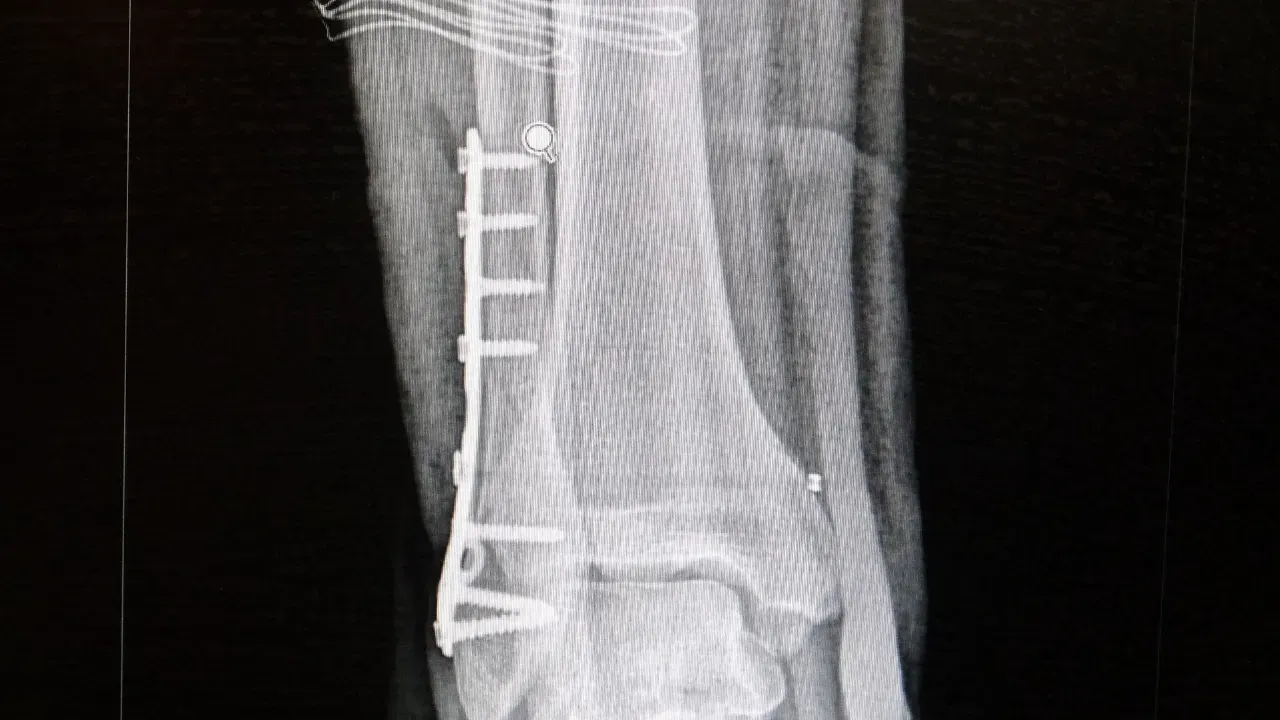

Ortopedi polikliniklerine en sık ayak bileği, diz ve omuz yaralanmalarıyla başvurulduğunu belirten Demirbaş, futbol nedeniyle yaralanma oranlarının da ilk sırada yer aldığını söyledi. Konuya ilişkin Demirbaş, "Futbolda menisküs yırtıkları, ön çapraz bağ yırtıkları, iç ve dış yan bağ yaralanmaları, aşil tendon kopmaları ve ayak bileği bağ yaralanmaları çok sık görülüyor. Ayrıca spora bağlı kırıklar da önemli bir yer tutuyor" ifadelerini kullandı.